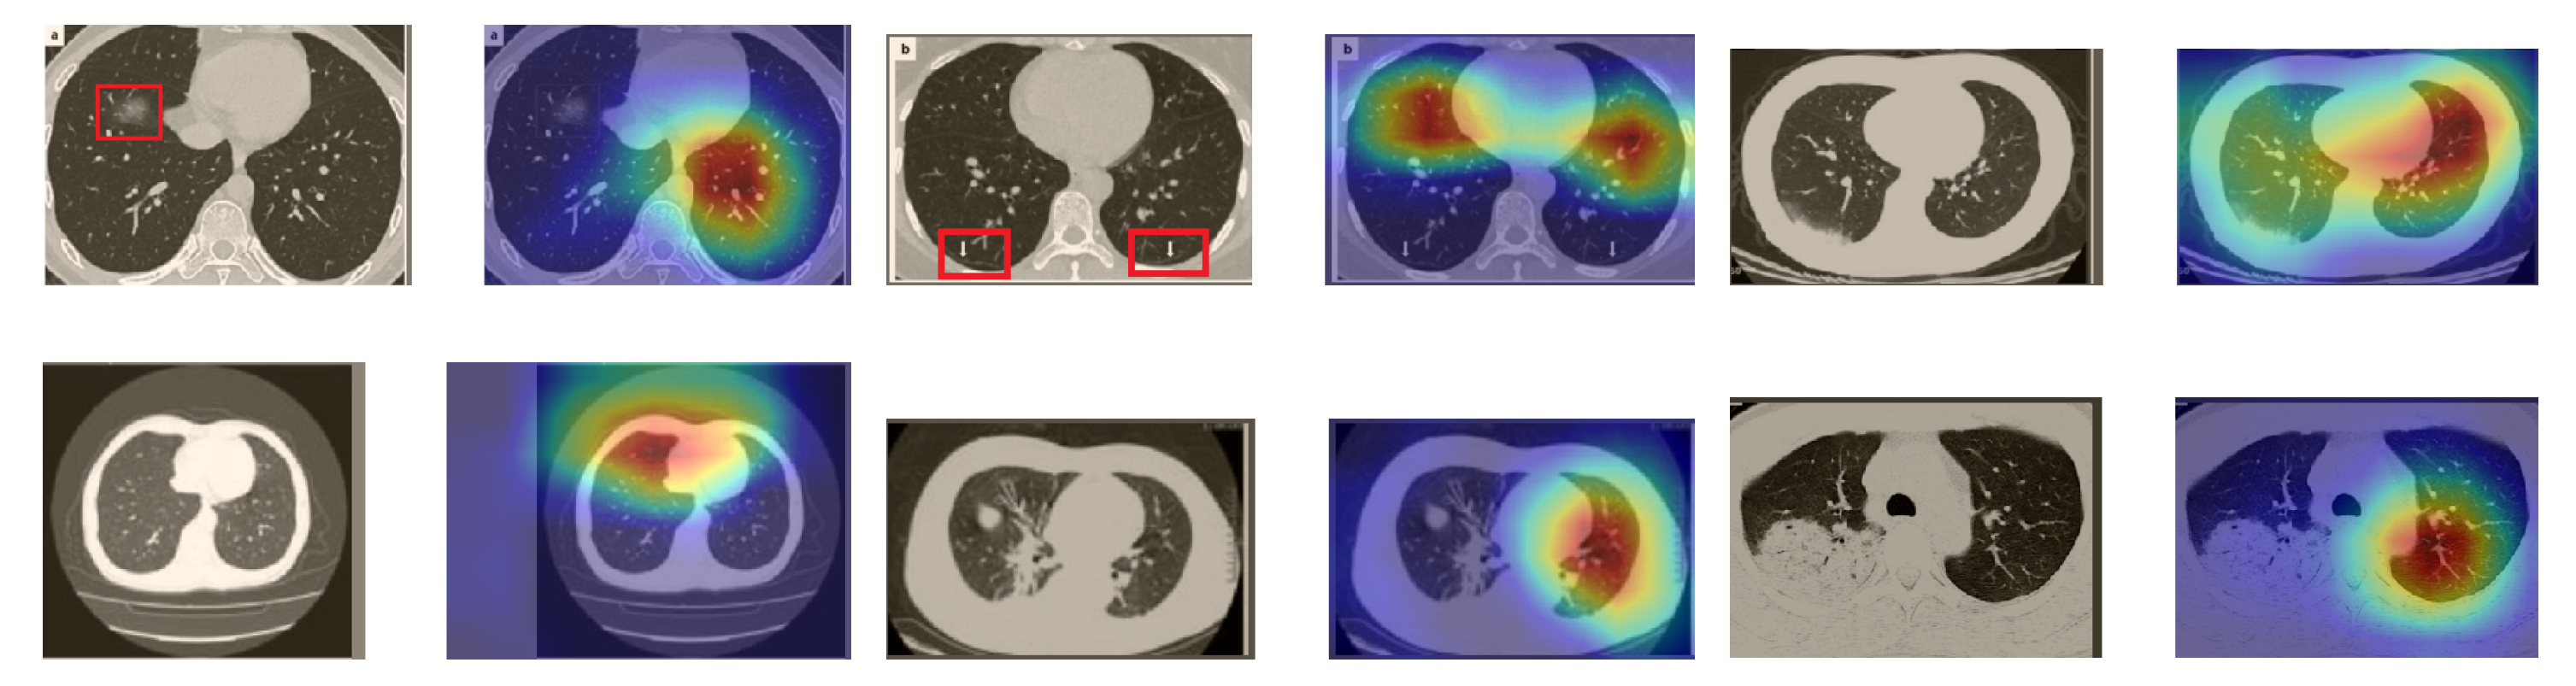

In a similar way, we considered classifying the test CT scans from the COVID-19 dataset by the DenseNet169 model, and highlight the important regions considered for predictions. We present samples of CT images and their localization maps in Figure 14. We can also see that our model is capable of detecting the COVID-19-related regions as annotated (small square in some images) by expert radiologists.

Figure 14.

Grad-CAM visualizations for sample CT images from the COVID19-CT dataset. Our DenseNet169 model correctly classified them as COVID-19 cases and highlighted the most relevant regions, as shown in the corresponding localization maps.